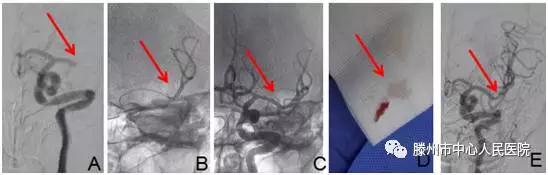

明確診斷為“腦栓塞”后,告知患者家人病情,建議機械取栓治療?;颊呒胰送夂螅痹\科護士迅速護送病人于9:35分進入介入手術(shù)室。再次與患者溝通病情并積極行手術(shù)準(zhǔn)備。9:40股動脈穿刺成功,造影見左側(cè)大腦中動脈M1段以遠閉塞(圖A),10點10分支架微導(dǎo)管到位(圖B)

10點19分Soltaire-AB支架到位打開后血流恢復(fù)(圖C),患者癥狀明顯減輕,等待5分鐘后,支架取出長條狀血栓(圖D),患者癥狀完全緩解,言語及肢體力量完全恢復(fù)正常。觀察10分鐘病情無反復(fù),再次造影左側(cè)大腦中動脈顯影完全正常(圖E),結(jié)束手術(shù),安返病房。